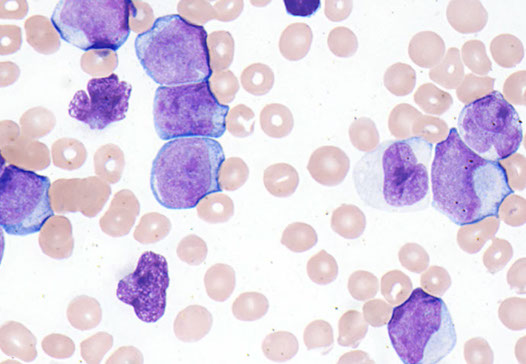

- Acute myeloid leukemia with mutated NPM1